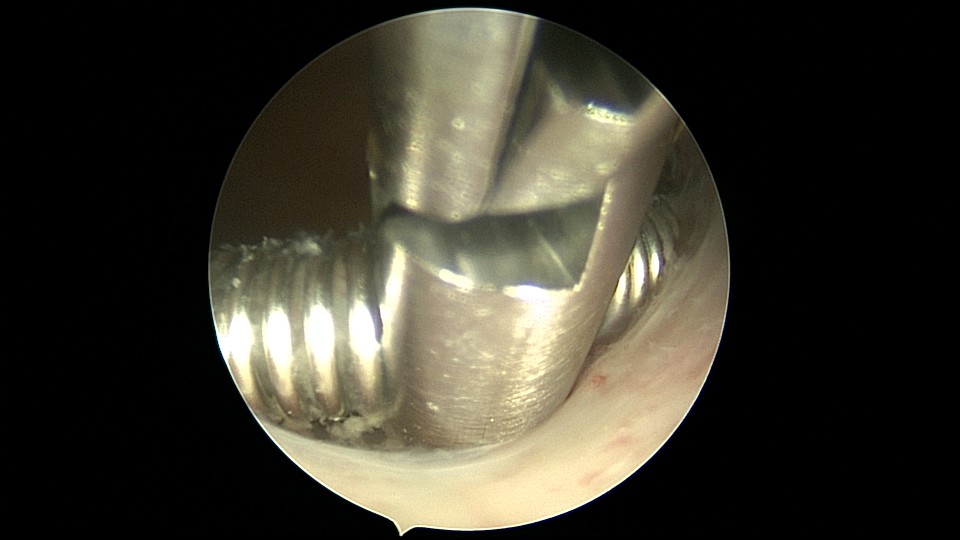

患者54岁,G1P1,剖宫产1次,安环30+年,绝经4年。40年前患者曾行左侧髋关节骨折手术,左下肢外展困难,患者肥胖,阴道很深,金属扩阴器和一次性扩阴器均无法暴露宫颈,用阴道内镜方式进入宫腔,但宫腔镜长度不够,远远能看见环,无法到达环的部位,再次试图暴露宫颈失败,用宫颈钳夹着阴道壁下拉,宫腔镜进入宫腔,但异物钳夹持力度不够,取出失败。用取环钩盲探沿宫腔镜外侧推挤进入宫腔,经历多次拧转,取环钩几乎向前弯成直角,直视下终于钩住节育环,掰直取环钩后缓慢拉出节育环,环变形。